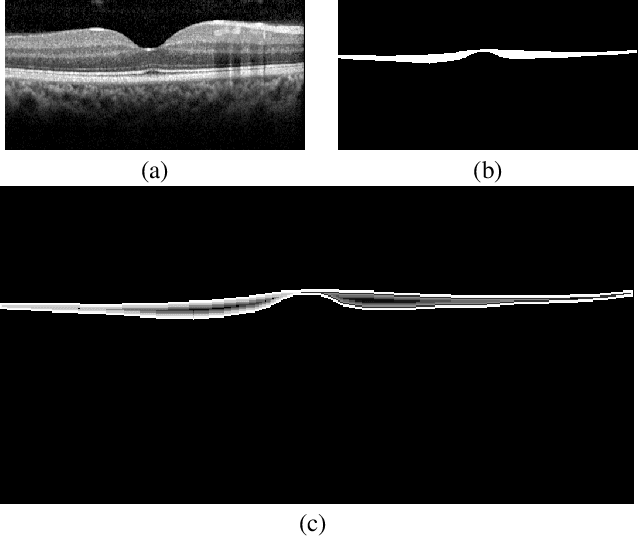

Abstract:The Henle's fiber layer (HFL) in the retina carries valuable information on the macular condition of an eye. However, in the common practice, this layer is not separately segmented but rather included in the outer nuclear layer since it is difficult to perceive HFL contours on standard optical coherence tomography (OCT) imaging. Due to its variable reflectivity under an imaging beam, delineating the HFL contours necessitates directional OCT, which requires additional imaging. This paper addresses this issue by introducing a shape-preserving network, FourierNet, that achieves HFL segmentation in standard OCT scans with the target performance obtained when directional OCT scans are used. FourierNet is a new cascaded network design that puts forward the idea of benefiting the shape prior of HFL in the network training. This design proposes to represent the shape prior by extracting Fourier descriptors on the HFL contours and defining an additional regression task of learning these descriptors. It then formulates HFL segmentation as concurrent learning of regression and classification tasks, in which Fourier descriptors are estimated from an input image to encode the shape prior and used together with the input image to construct the HFL segmentation map. Our experiments on 1470 images of 30 OCT scans reveal that quantifying the HFL shape with Fourier descriptors and concurrently learning them with the main task of HFL segmentation lead to better results. This indicates the effectiveness of designing a shape-preserving network to improve HFL segmentation by reducing the need to perform directional OCT imaging.